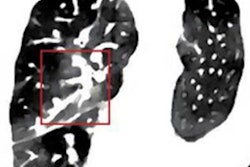

The proton treatment plan based on the DirectSPR method (left) results in substantially reduced dose to healthy tissue compared with a plan based on conventional lookup tables (dose difference map, right). Image courtesy of OncoRay/Christian Hahn, Nils Peters.The advantage of proton therapy over conventional x-ray radiotherapy lies in the narrowness of the particle's Bragg peak -- the distance over which it deposits its energy in a medium. Whereas the energy delivered by photons falls off gradually with distance, the dose distribution for charged particles such as protons rises sharply beyond a certain depth and then drops even more suddenly. The exact position and shape of the peak depend on the initial velocity of the particles in the beam and on the properties of the tissue along its trajectory.

Working with colleagues from the German Cancer Research Center (DKFZ) in Heidelberg, the OncoRay team validated the accuracy of the new approach, called DirectSPR, in a phantom and biological tissues and found that safety margins around the treatment volume could be reduced by 35% to 40%. The reduced margins achieved with DirectSPR are now applied clinically at UPTD. "The range accuracy, which has remained practically unchanged for more than 30 years, is thus for the first time significantly improved," Richter said.